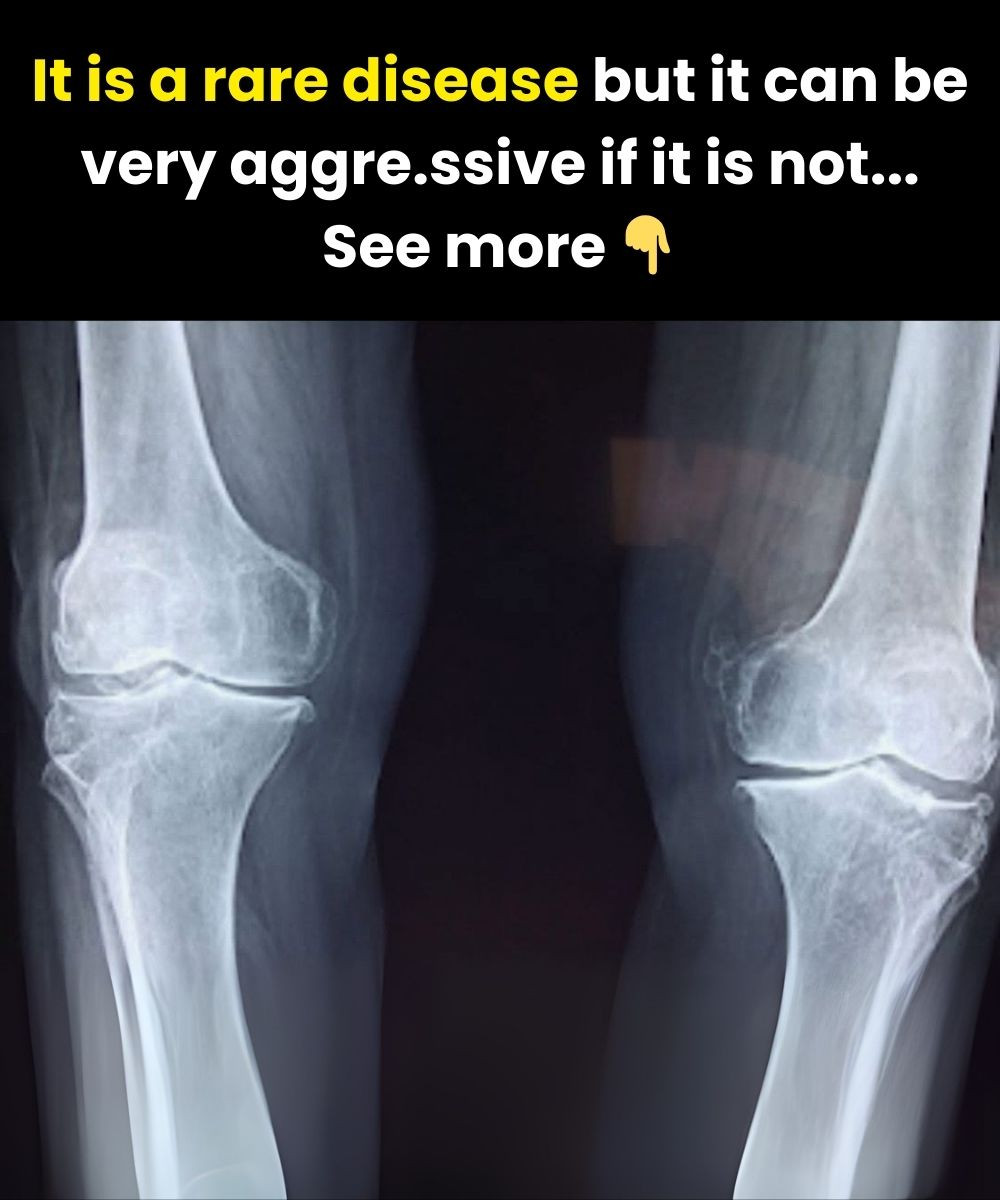

Osteoporosis, often called the “silent bone disease,” is one of the most popular health issues affecting older adults, especially women after menopause. The condition lessens bones, making them fragile and more likely to break. Because osteoporosis grows slowly and may not cause obvious symptoms at first, many people do not realize they have it until a fracture happens. Understanding the early signs and taking preventive measures are key to protecting your bone health.

Early Signs of Osteoporosis

Unlike many diseases, osteoporosis does not always show obvious symptoms in its early stages. However, there are certain war:ning signals you should draw attention to:

Back Pain or Sudden Spinal Discomfort

Compression fractures in the vertebrae can cause unpredicted back pain. This is often one of the first signs of bone weakening.

Loss of Height

Many people with osteoporosis notice that they become shorter over time. A loss of more than 2–3 centimeters may suggest spinal bone loss.

Stooped Posture